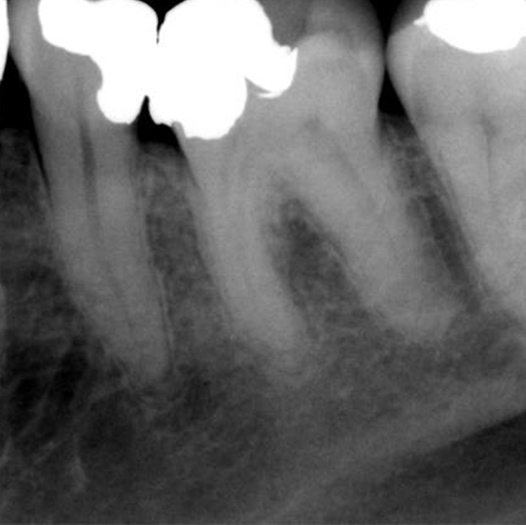

Before

Before Root Canal treatment